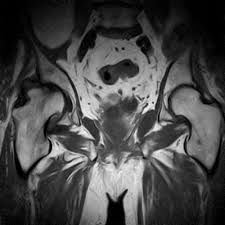

Az MRI még részletesebb, tisztább képet ad. A felső képen egy komoly gerinccsatorna szűkület látható, feltehetően a kitüremkedő porckorong, vagy egyéb, nem oda való képlet (pl.:daganat) miatt.

A gyakorlatlan szemnek egy kis segítség: az alsó képen a medence és a csípőizület metszete látszik.